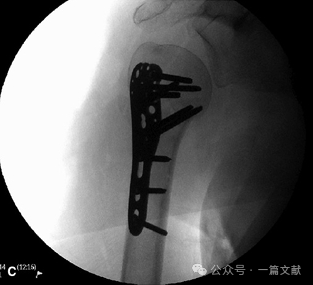

肩关节外展30-90°拍摄,此位片一般用于骨折复位且内固定以后,来评估术中复位以及内固定位置。主要可以观察:盂肱关节匹配情况,大、小结节复位情况,肱骨近端矢状面的对位情况,肱骨头后倾角,钢板位置以及螺钉长度。如下图:

体位与拍摄角度: